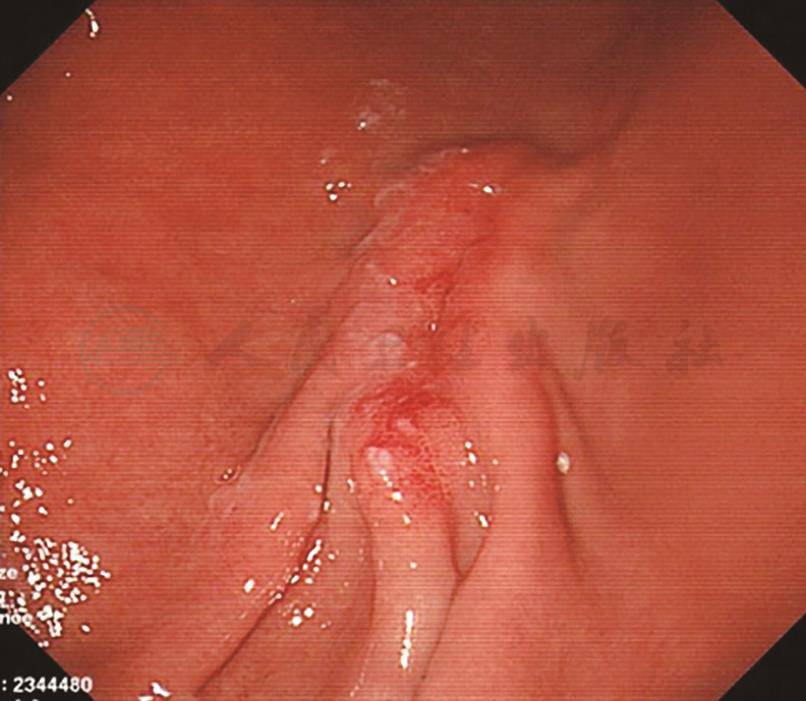

2.胃镜检查

镜下见胃体上部大弯侧可见1枚直径约0.5cm的山田Ⅰ型息肉;窦体交界大弯侧可见2条黏膜皱襞,粗大僵硬,范围约4cm×2cm,表面黏膜粗糙、糜烂(图8)。胃镜下诊断:胃窦体交界皱襞粗大,胃息肉,慢性浅表性胃炎。活检组织幽门螺杆菌(helicobacter pylori,HP)阴性。

活检标本(窦体交界)病理表现:印戒细胞癌;免疫组化染色:CK、EMA、CD68、Ki-67均阳性;特殊染色:AB-PAS阳性(图9)。

图8 胃镜检查镜下表现

图9 活检标本(窦体交界)病理表现(AB-PAS染色,400×)